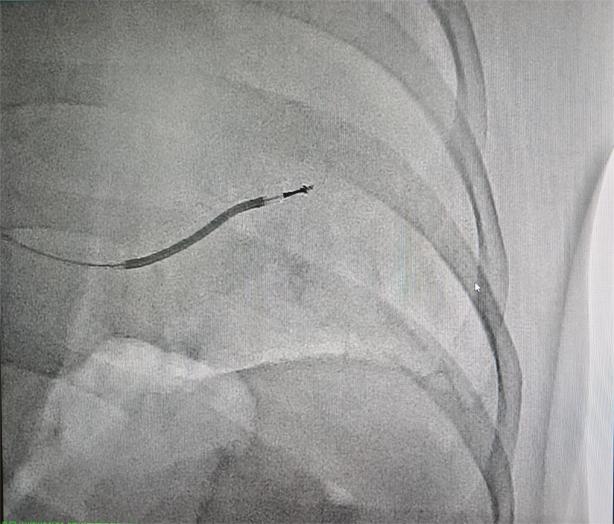

手术由朱舜明主任、唐治国主治医师主刀,在导管室团队密切配合下,通过微创方式将ICD电极精准放置于患者心脏右心室间隔部,并完成设备调试。术中测试显示ICD识别及除颤功能良好,手术历时约1小时顺利完成。术后患者生命体征平稳,目前已转入普通病房进一步康复。